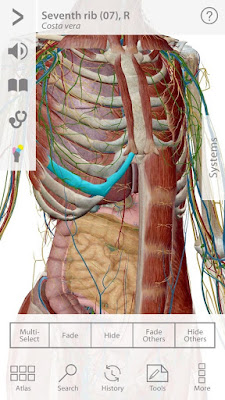

-Visible Body ® là một công ty phát triển phần mềm tạo giải phẫu học từng đoạt giải thưởng và các sản phẩm học tập sinh lý học.Trong đó, phần mềm Visible Body Human Anatomy Atlas là một trong những thành công nhất. Ứng dụng này phát triển trên cả nền tảng máy tính và di động.Với những hình ảnh sinh động và trực quan, thật dễ dàng để bạn có thể làm chủ kiến thức giải phẫu cơ thể người.

-Ứng dụng này bao gồm các mô hình giải phẫu 3D với hơn 6000 hình ảnh 3D từ tất cả các hệ thống cơ thể:Cá nhân mình thấy đây là một ứng dụng rất hay, ứng dụng được viết bằng tiếng anh rất tiện cho việc học từ ngữ chuyên ngành luôn ( nếu tiếng anh của bạn mù tịt như mình thì có thể vào đây dịch ) thứ hai ứng dụng này có dung lượng tuy nhỏ (chỉ hơn 200 mb) nhưng đầy đủ các chức năng của một ứng dụng giải phẫu 3D chuyên nghiệp như xoay mô hình 360o , ẩn các bộ phận được chọn, vẽ thêm chi tiết vào mô hình vv… đặc biệt khi bạn chọn vào một bộ phận, sẽ có đường chỉ dẫn đến bộ phận đó và có phần miêu tả khá đầy đủ (cũng bằng tiếng anh ) ở phía dưới.